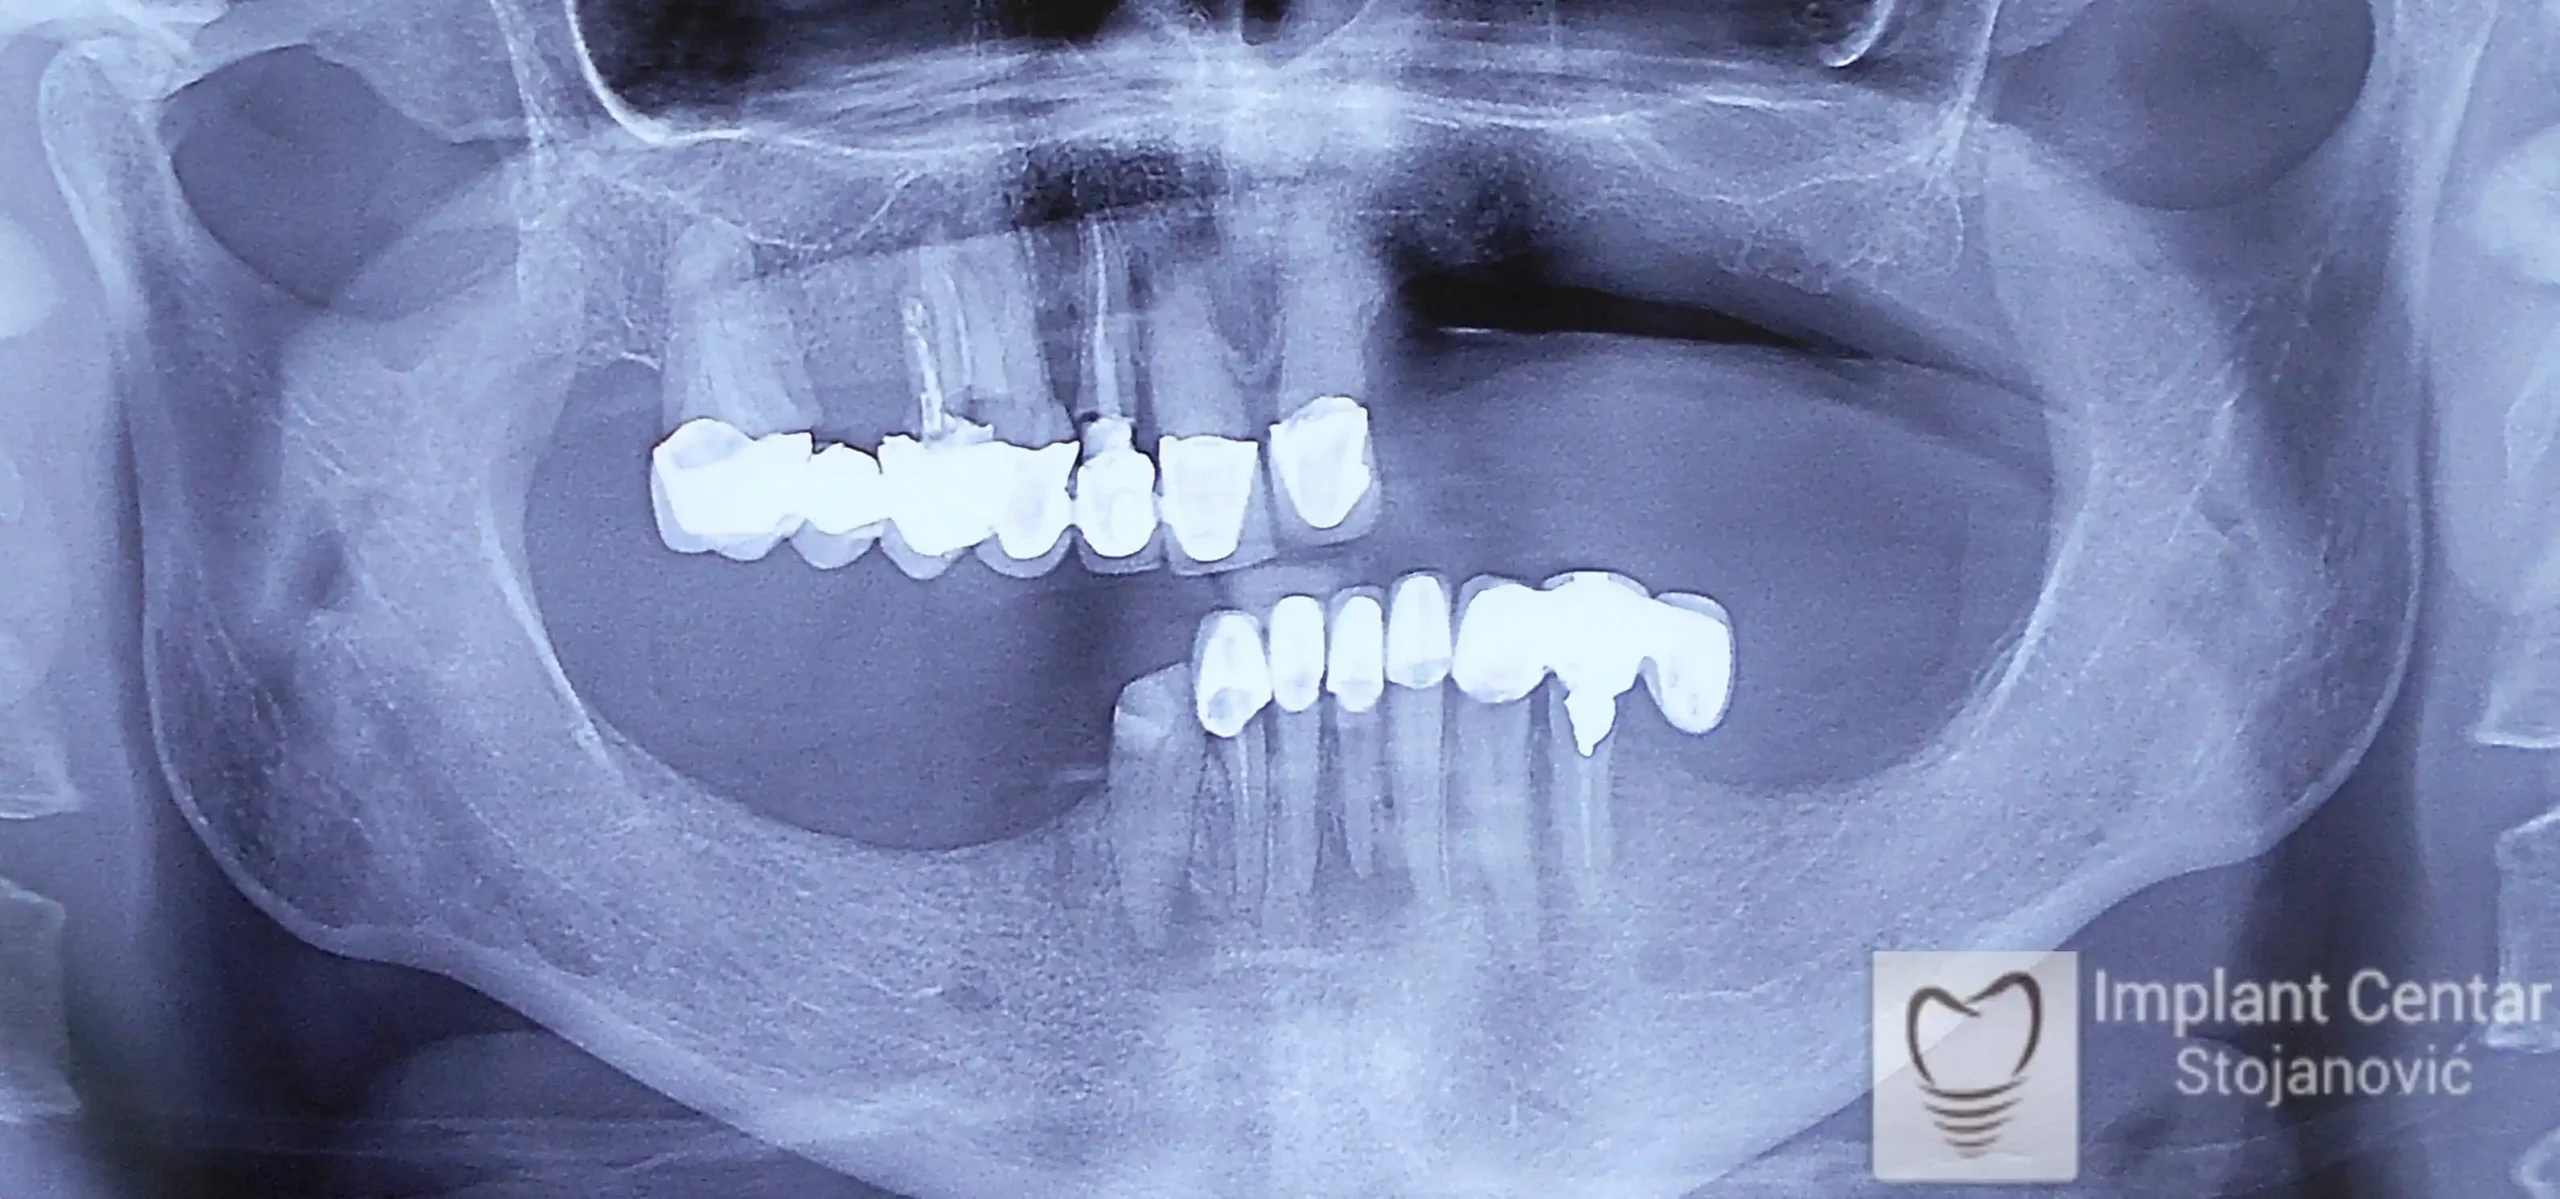

Na slici 1. slici 2. vidi se početno stanje — pacijent je imao prirodne zube, ali samo izradom novih mostova nije bilo moguće postići normalan odnos gornjih i donjih zuba (eugnatan zagrižaj).

Zbog toga je plan terapije uključivao vađenje svih preostalih zuba i ugradnju implantata u gornjoj i donjoj vilici. U gornjoj vilici postavljena su i dva tuberopterigoidna implantata, kao zamena za sinus lift proceduru, što se može videti na ortopan snimku nurađenom odmah nakon ugradnje (slika 3).